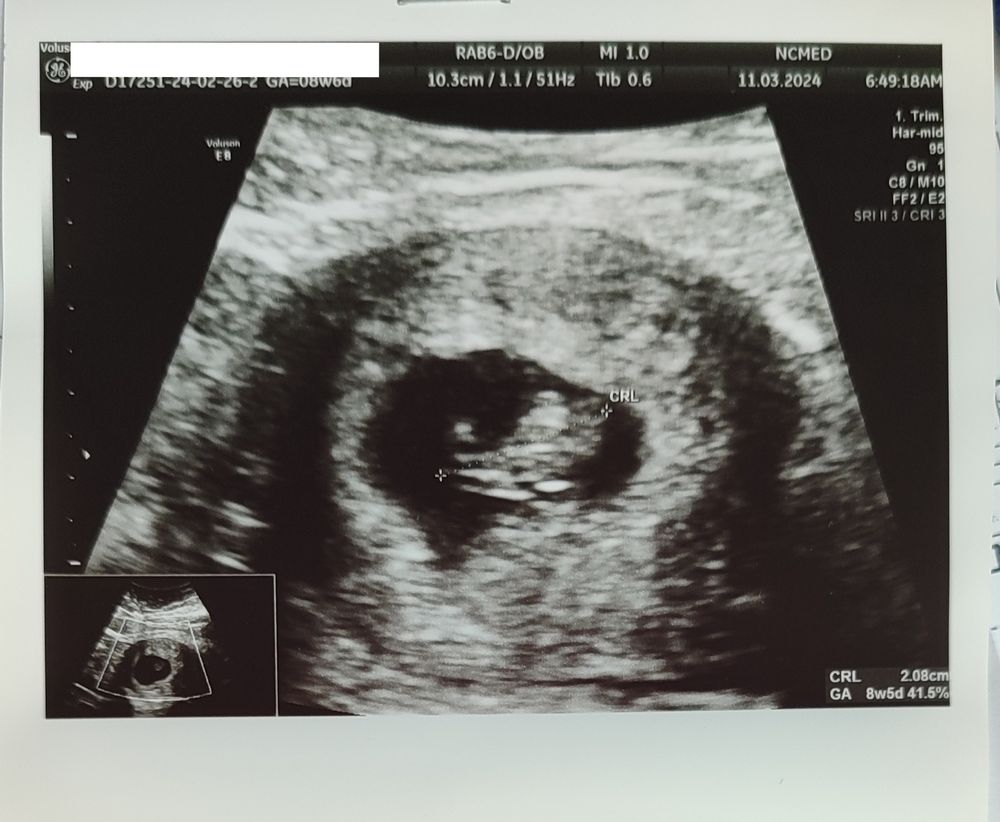

УЗИ 8 недель 5 дней

Смотрели уже через живот и всё прекрасно видно. КТР 21 мм, ВДПЯ 38 мм, ЖМ 3,3 мм. Сердечко стучит быстро быстро, 175 ударов в минуту.